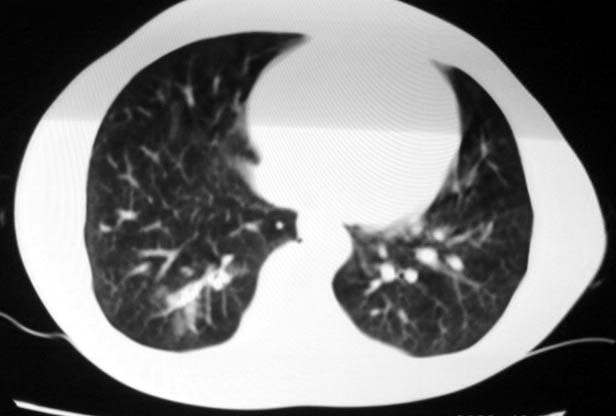

标题: CT5614:外伤病人男,20岁,右上腹痛.余肺野(-)

最后一幅图像病灶区可分椎旁肋骨骨折可能?请示骨窗,结合外伤史考虑右下肺挫伤。

最后一幅图像示椎旁肋骨走形欠自然,请示骨窗,结合外伤史考虑右下肺挫伤。

支持肋骨骨折,肺挫裂伤。